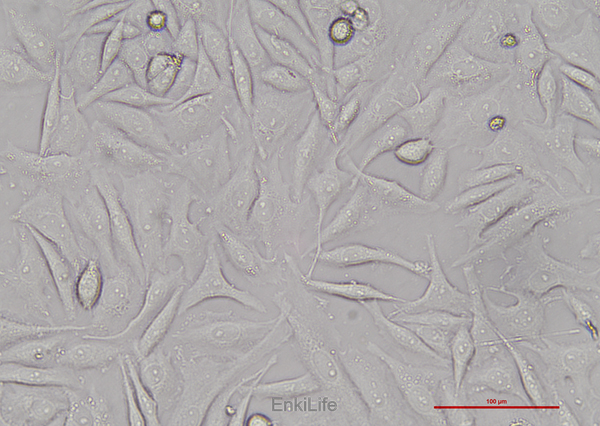

SiHa细胞是建自一个日本病人的外科手术的原位组织样品。电镜观察表明,在SiHa细胞连接处有典型的桥粒,在SiHa细胞胞质中有丰富的张力丝。在裸鼠中,SiHa细胞能形成低分化的表皮样癌(Ⅲ级);SiHa细胞中,癌基因PRB和p53阳性。

贴壁细胞

上皮细胞样